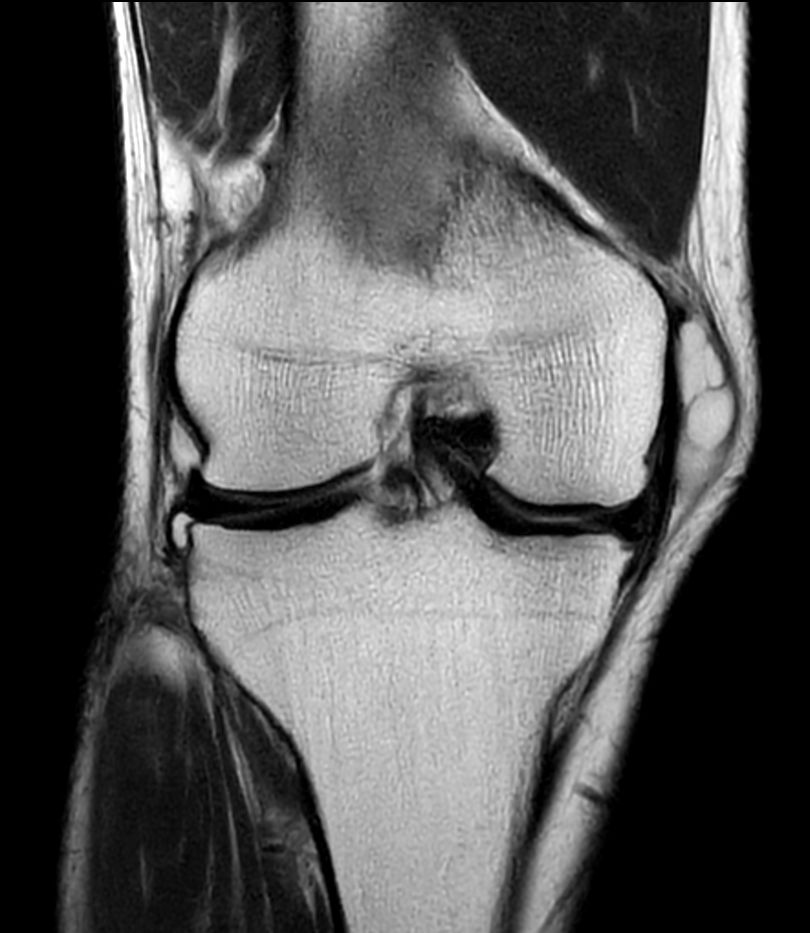

T2w TSE - Compressed SENSE